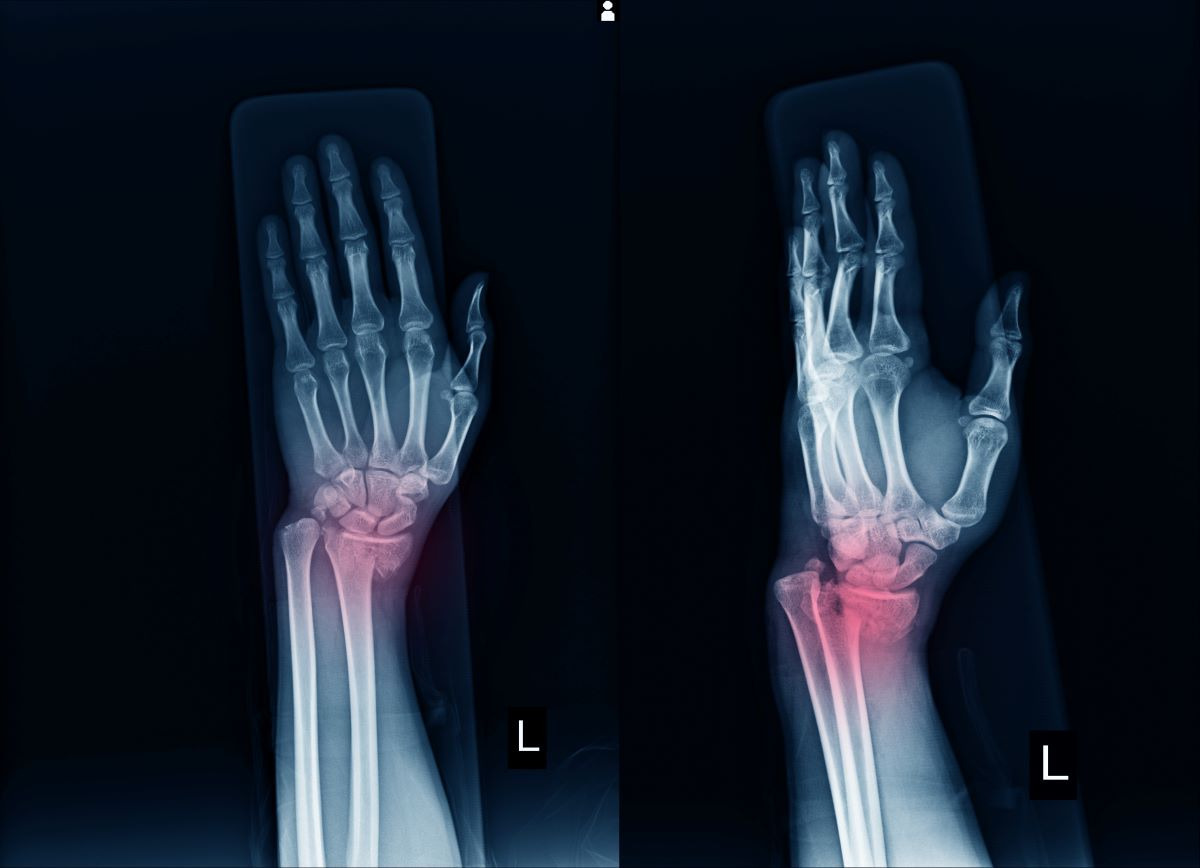

손목 골절 완치 기간과 재활치료, 요골 골절 깁스기간

손목 골절은 손목 관절을 이루는 요골·척골 중 특히 요골 원위부 골절이 가장 흔하게 발생합니다. 넘어지면서 손을 짚거나, 교통사고·스포츠 손상 등 외부 충격으로 뼈가 부러질 수 있습니다. 골절은 단순히 뼈만 부러지는 것이 아니라 주변 인대·근육·신경까지 손상될 수 있어 치료와 회복에 긴 시간이 필요합니다.

- 치료 방법: X-ray 확인 후 뼈를 맞추는 정복(整復) → 깁스로 고정

요골 골절 깁스기간, 주의사항

- 단순 골절: 4~6주 깁스

- 복합 골절: 6~8주 이상 깁스 또는 보조기